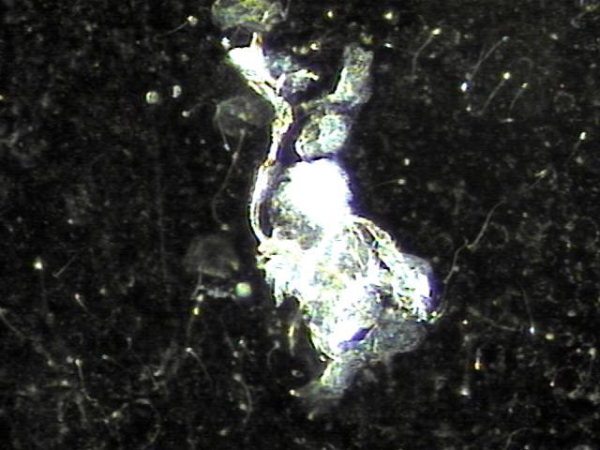

내원 첫날 전립선의 표적 치료후 치료된 정낭의 혈정액과 정자들과 염증들의 현미경학적 자료입니다.

This is a microscopic image taken after your first targeted prostate treatment, showing improvement in the seminal vesicle.

The blood-tinged fluid (hematospermia), sperm, and inflammatory cells have been successfully treated.